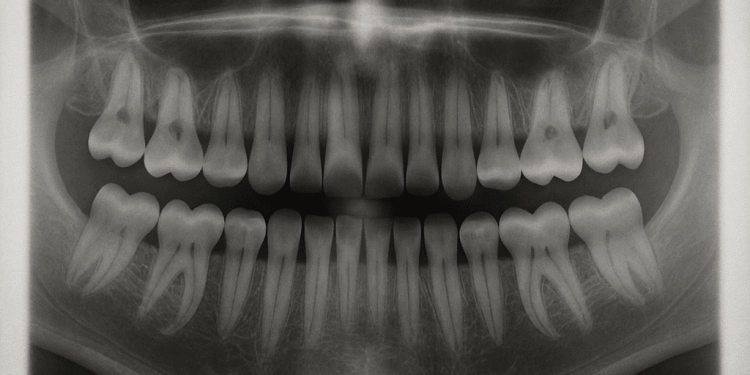

Хиймэл шүд зүүж, түүндээ дасах эсвэл ясаа өрөмдүүлж имплант шүд суулгах зэрэг арга удахүй ард хоцрох бололтой. Учир нь Японы эрдэмтэд насанд хүрсэн хүмүүст шинэ шүд ургуулах эм бүтээж байгаа бөгөөд 2030 он гэхэд нийтийн хэрэглээнд оруулна гэсэн төлөвлөгөөтэйгээр ажиллаж байгаа ажээ Энэхүү эмчилгээ нь шүдний өсөлтийг хариуцдаг генд төвлөрч буй бөгөөд одоогоор эмнэлзүйн туршилт хийж эхэлжээ.

Японы Осака хотын Китано эмнэлгийн Анагаах ухааны судалгааны хүрээлэнгийн ахлах эрдэмтэн, доктор Кацу Такахаши олон жилийн турш шүдний хөгжлийн генетикийн зарчмуудыг судалж ирсэн бөгөөд 2021 онд USAG-1 гени амьтны шүдний генийн ургалтад хэрхэн нөлөөлж болохыг туршсан байна.

Тодруулбал, судлаачид USAG-1 уураг нь хулганын шүдний өсөлтийг хязгаарлаж чаддаг болохыг тогтоожээ. Тиймээс уураг үүсэхгүй байх нь шүдийг ургуулахад хүргэж болзошгүй гэж тэд дүгнэсэн байна . Тус багийнхан уургийг хаах эм бүтээж, улмаар хулганад шинэ шүд ургуулж чадсан аж.

Эрдэмтэд эмийн эмнэлзүйн туршилтыг эхэлснээ, таван жилийн дотор нийтийн хэрэглээнд бэлэн болгох зорилт тавьсанаа зарлав.

Эрдэмтэд хүн төрөлхтөнд сүүн шүд, ясан шүдний дараагийн гурав дахь шүд нь нахиа хэлбэрээр байдаг бөгөөд шаардлагатай бол ургахад бэлэн байдаг гэж үзэж байна.

Доктор Такахаши хэлэхдээ, түүний өмнөх судалгаагаараар гурав дахь шүдний нахиаг генийн зөв зохицуулалтаар идэвхжүүлснээр шүд дахин ургах боломжтой гэв.